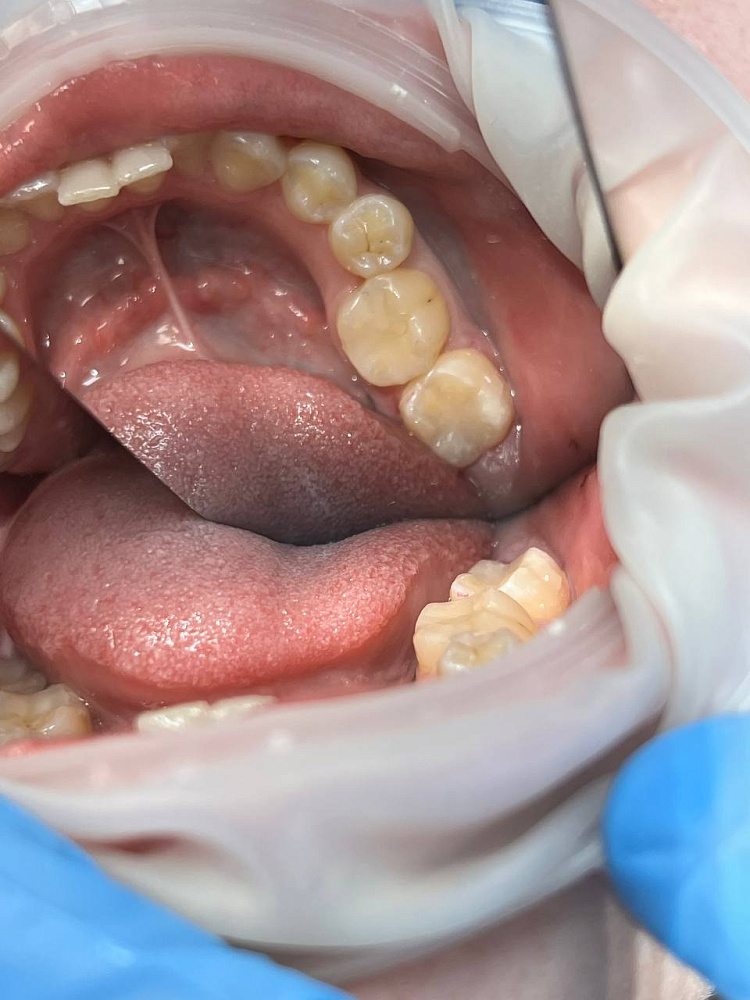

Лечение кариеса 36 зуба было выполнено под анестезией с изоляцией области. После удаления кариозных тканей и проверки кариес-маркером сформирована полость и выполнена реставрация композитом Estelite. Восстановлена анатомия жевательной поверхности и контактный пункт. Завершили работу финишной полировкой.